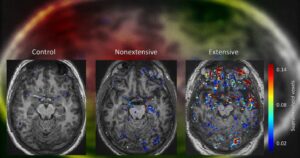

Исследование ирландских ученых показало, что у спортсменов из контактных видов спорта возникают нарушения гематоэнцефалического барьера, которые сохраняются и после прекращения занятий. Исследователи обнаружили это, проведя МРТ с контрастированием спортсменам, которые не практиковались в среднем 12 лет. У них наблюдали проникновение контрастного вещества в ткани мозга: в особенности пострадало левое полушарие. Работу опубликовали в Science Translational …